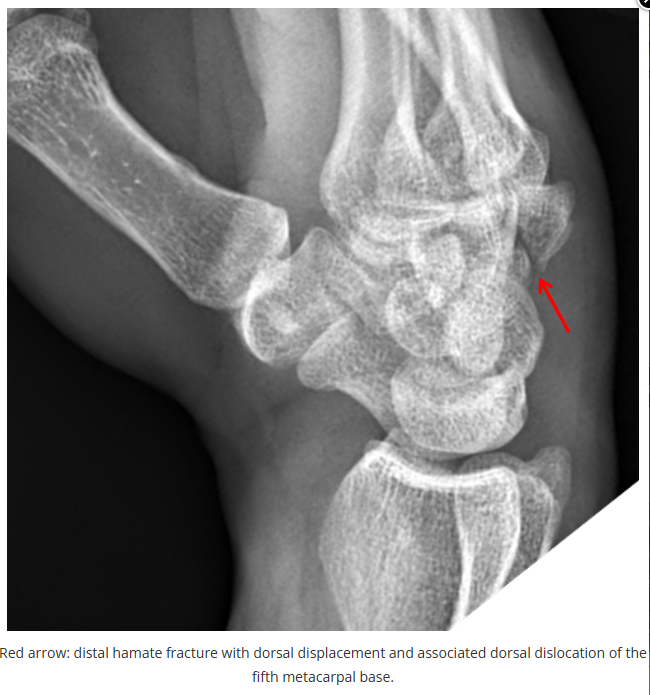

X线读片是骨科医生的基本功。

今天是腕部与手的X线片。所有X线片都

带有标注和说明

,可以选择长按图片,

自动翻译相关说明

进阶篇